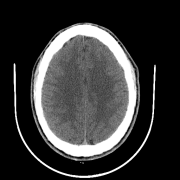

We also include visual examples of consecutive CT slices in Fig. 3. In Scan 1, the baseline Att-MIL produces a wrong prediction at scan level. When using SA, the prediction is correct since dependencies between adjacent slices have been learned. In Scan 2, both models produce correct predictions at scan level, but SA-DMIL is more accurate at slice level. This occurs thanks to the SA loss, that turns the attention scores into smoother values and, therefore, avoids random jumps up and down the decision threshold.

|

| Ground truth | ICH | ICH | Normal | Normal | Normal | ICH | ||

| Att-MIL () [15] | Normal | ICH | ICH | ICH | Normal | ICH | ||

| SA-DMIL- () | ICH | ICH | Normal | Normal | Normal | ICH |